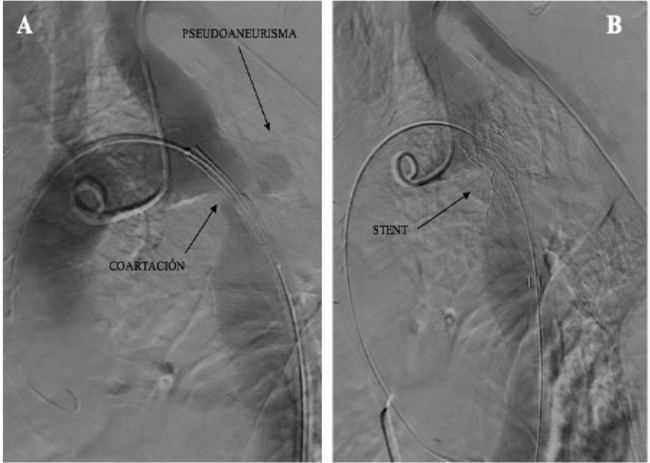

Se efectuó el procedimiento bajo neuroleptoanalgesia, con monitoreo central continuo de la presión diferencial y un marcapasos rápido durante la colocación de la endoprótesis. Se utilizó un catéter balón AltoSa XL Gemini 18 mm de diámentro y 50 mm de longitud (AndraTec GmbH, Koblenz, Alemania) sobre el que se montó un stent autoexpandible recubierto Covered Andrastent 48XL (stent de cromo-cobalto con diseño de celdas semiabiertas cubierto con PTFE, AndraMed GmbH, Reutlingen, Alemania). Una vez liberado se realizó una angiografía de control y se registraron presiones arteriales diferenciales en pull back. El stent recubierto pudo ser colocado en la posición correcta, y el gradiente previo de 60 mmHg disminuyó a 15 mmHg (Figura 2).